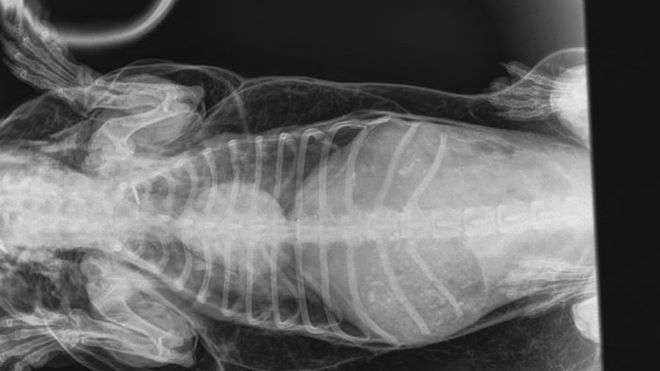

▼獸醫Michelle Coward診斷後,發現Trevor有很嚴重的皮下氣腫問題。但牠身上沒有傷口,空氣是如何進入肌肉和皮下組織的呢?Michelle找不到答案,只能推斷可能是氣管內部有損傷,才會導致空氣進入體內。